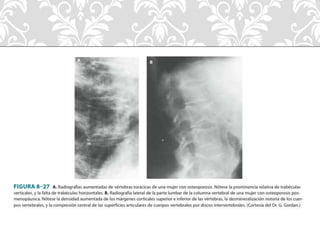

• Clínico: Historia clínica, exploración física.

• Radiografía. Cuando existe entre 30-40% perdida de masa ósea.

• Estudio radiológico (rarefacción generalizada).

• Cortical delgada y deformada.